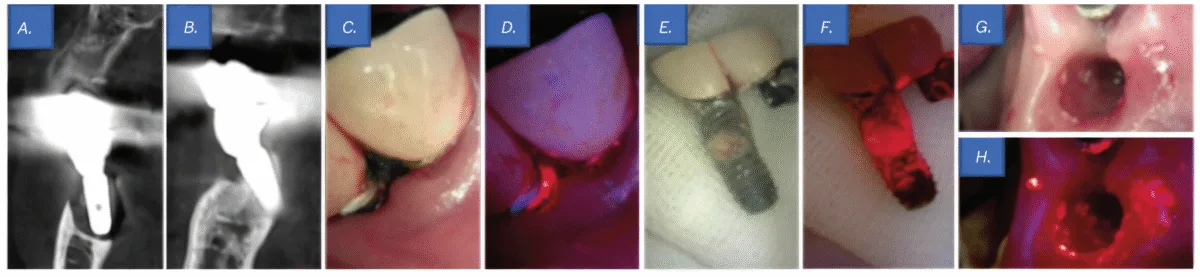

An 86-year-old feminine affected person initially visited a neighborhood dental clinic, the place she was suggested to hunt analysis and remedy at a college hospital because of extreme bone loss across the decrease left implant. She subsequently offered for her first go to to the Division of Periodontology at Gangnam Severance Dental Hospital. The affected person had no vital underlying medical situations apart from hyperlipidemia.

Scientific examination revealed a probing depth of 12 mm round implant No. 19, accompanied by lively pus discharge above the gingival margin (Determine 5C). Moreover, QLF imaging detected purple fluorescence from porphyrins, indicating a mature biofilm (Determine 5D). Cone-beam computed tomography revealed bone loss round implant Nos. 18 and 19, resulting in a prognosis of peri-implantitis (Figures 5A-5B). Notably, implant No. 19 exhibited bone loss extending to the apex, and through prosthesis elimination, it was spontaneously exfoliated (Determine 5E). Though no vital biofilm was noticed macroscopically on the tissue and fixture surfaces (Determine 5G), QLF analysis detected porphyrin fluorescence, confirming the presence of a biofilm (Figures 5F-5H).

Subsequently, a sulcular incision was made utilizing #15T and #12 blades, adopted by socket curettage with tetracycline. The wound was then closed utilizing a figure-eight suture method with 4-0 absorbable artificial sutures (Coated Vicryl™, Ethicon, Johnson & Johnson, Somerville, New Jersey).

One week after the implant elimination process, the affected person returned for suture elimination. Therapeutic was passable, with no notable issues. On the 6-month follow-up, the affected person reported no vital discomfort, and general oral well being was secure in comparison with the preoperative situation.